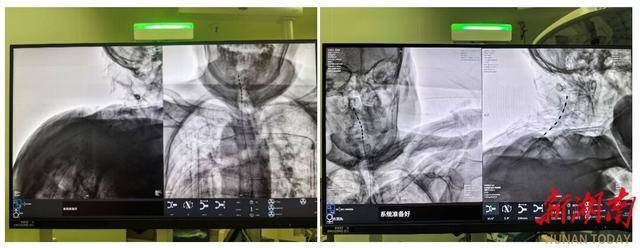

面对两位高龄且身体机能脆弱的患者,中南大学湘雅三医院疼痛科胡蓉教授团队经过严密评估,最终于1月中旬为其成功实施了“局麻下C臂引导下脊髓电刺激术(SCS)植入术”。这项被称为神经调控领域“减痛黑科技”的技术,其原理在于:将微细电极植入脊髓硬膜外腔,通过发出微弱电脉冲,在疼痛信号传向大脑的路径上进行“精准拦截”,从而阻断痛感。

(C臂透视示术中电刺激已成功置入)

手术在局麻下进行,老人全程清醒。术中,当电极启动测试时,陈奶奶激动地反馈:“麻到了!颈根和肩胛都不痛了!”这种即时反馈确保了电极能够百分百覆盖痛区。术后一周,两位老人的疼痛视觉模拟评分(VAS,0分为无痛,10分为剧痛)从术前的8-9分骤降至2-3分,睡眠质量和情绪状态得到了质的改善。